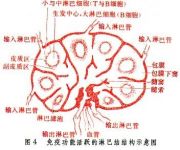

| 2021年7月26日 (一) 20:01 | 免疫功能活跃的淋巴结构示意图.jpg (文件) |  |

26 KB | 77921020 | Uploaded with SimpleBatchUpload | 3 |